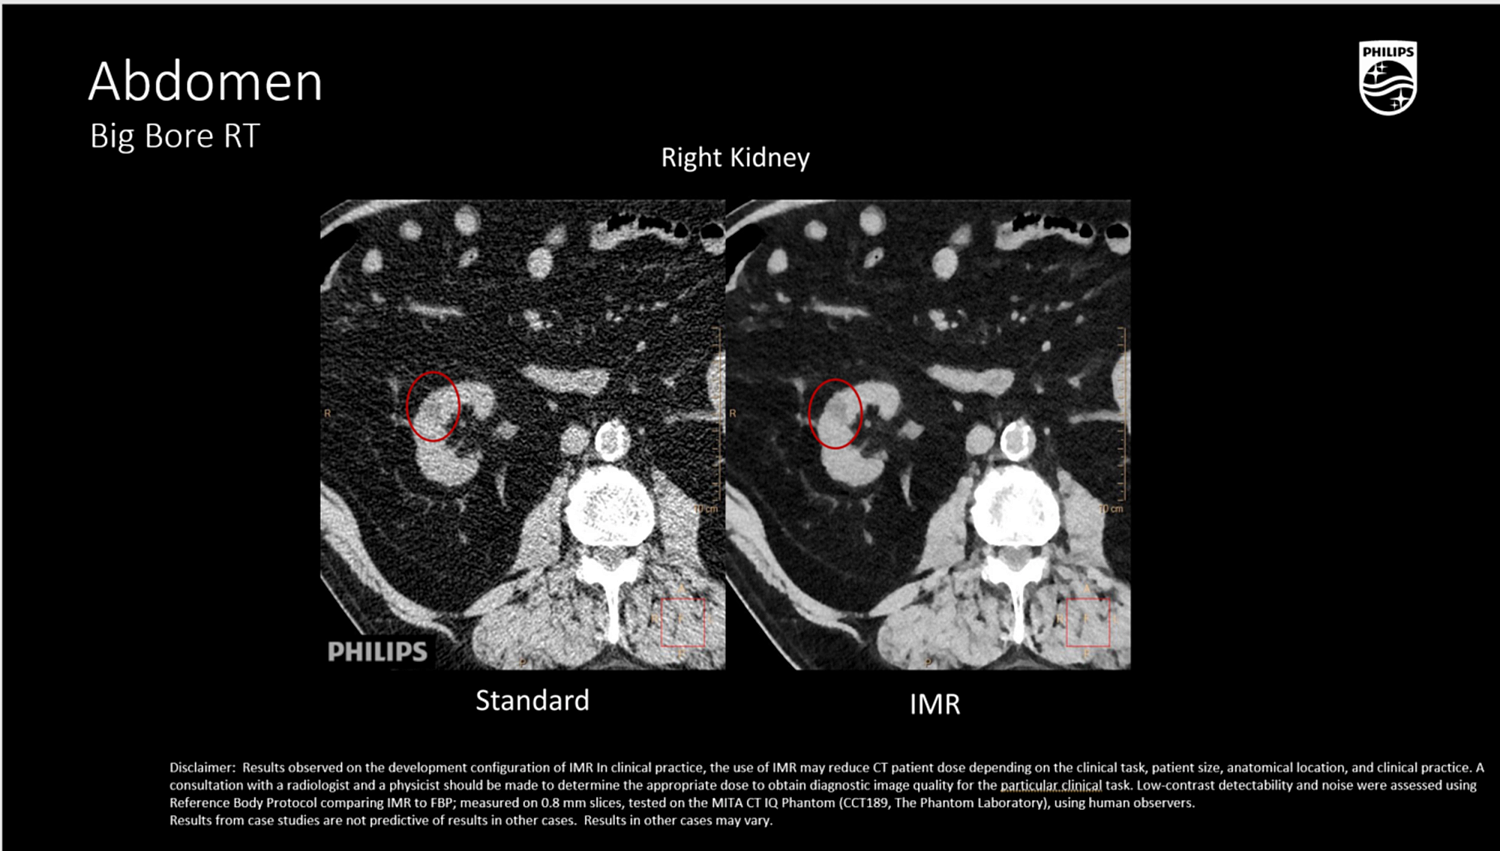

Клинические изображения

Абдоминальная и тазовая локализация

- Визуализация мягкотканных опухолей (печень, почка, поджелудочная железа, органы таза) с контурированием OAR,